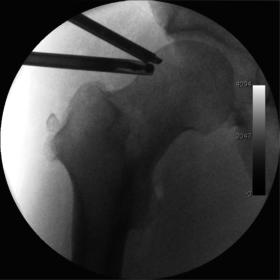

The procedure is performed with the patient asleep (general anaesthetic) or under spinal anaesthesia. There are two widely used methods, one with the patient on their back (supine) and the other on their side (lateral decubitus). Which is used is down to the surgeon's preference. To gain access to the central compartment of the hip joint (between the ball and socket), traction is applied to the affected leg after placing the foot into a special boot. (See fig. 2) There is specifically designed equipment for this, although some surgeons use a 'traction table', initially designed to help in the operative fixation of broken thigh and lower leg bones. The amount of traction (or pull) needed is assessed with the help of fluoroscopy (low-dose portable x-ray). (See fig. 3) It is usually not possible to distract the ball from the socket with traction alone by more than a few millimetres. Once the surgeon is happy that he will be able to gain access to the hip joint (i.e. the ball will distract from the socket by a small amount), the patient is then painted with antiseptic and the surgical drapes applied.

The next step is to insert a fine needle under x-ray guidance into the hip joint. This breaks the 'suction seal' of the joint and allows further distraction if necessary (see fig 4). The surgeon wishes to see the ball move out the socket by approximately 1 cm, so that access to the hip joint can be achieved with minimal risk of damage to the joint surfaces. Most surgeons will inject fluid into the joint at this stage, again to ensure that there is enough space between the ball and socket for safe instrument access. This needle is then removed. The next step is placement of the 'portals', or the small holes made to pass instruments into the joint. This is achieved by again passing a fresh hollow needle into the joint under x-ray control, usually in a slightly different position. The reason for this is so the surgeon can ensure that the needle, and subsequent cannulae do not penetrate and damage the acetabular labrum or cartilage joint surfaces (see fig. 5). Again, surgeons will have their own preferences as to their preferred placement. Through this hollow needle, a long thin flexible guide wire is passed into the joint, and the needle is removed over it, leaving the guide wire in situ. A small cut in the skin is made around the wire, to allow for larger cannulae to be placed over the wire through the portal. The wire therefore guides the larger cannulae into the joint. The most common external diameters of cannulae used are between 4.5 and 5.5 mm. Once the surgeon is satisfied that the cannula is in the correct position, by a combination of feel and x-ray guidance, the guide wire can be withdrawn. Once the first portal is correctly placed, any further portals may be created once the camera is in position, to ensure that they are placed with minimal risk to the joint surfaces. This process can be repeated to gain as many points of entry to the hip joint as the surgeon requires, normally between two and four. Certain of these entry points will be used for the viewing arthroscope and others for operating instruments.